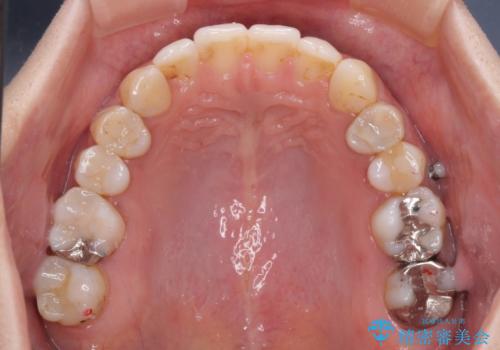

長時間のマウスピース装着と、患者様自身でのゴムかけに協力いただき、自然な口元に仕上げることができました。

気になっていた変色した歯もオールセラミッククラウンで本物の歯のようになり、患者様には大変満足していただきました。